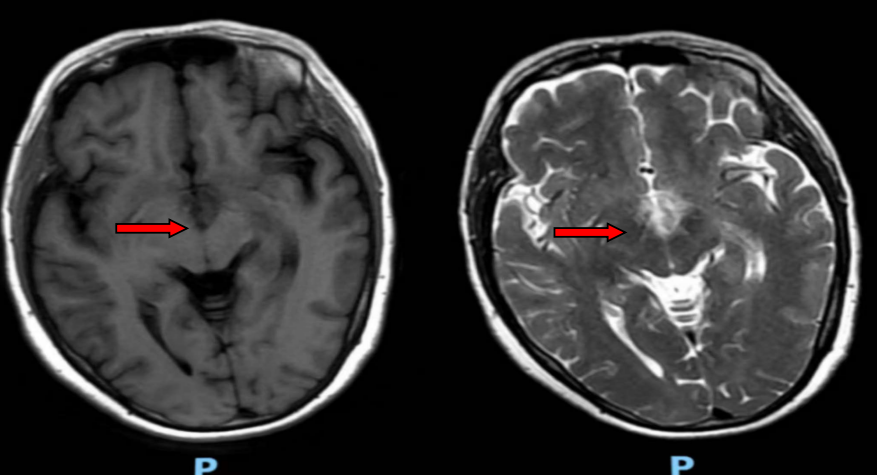

风湿免疫科欧阳楚君副主任接诊后,发现患者自身抗体谱更符合干燥综合征,需鉴别颅内感染与原发病活动,随即安排头颅MRA、腰椎穿刺及脑脊液相关检测。鉴于病情复杂,科室迅速启动多学科协作诊疗(MDT),联合神经内科、呼吸科等多科室专家会诊。结合影像学双侧丘脑及颈髓异常信号、脑脊液AQP4抗体阳性结果,最终明确诊断为“干燥综合征合并视神经脊髓炎”。

△治疗前头颅MR提示双侧丘脑内侧、灰结节脑实质异常信号影

治疗后双侧丘脑内侧、灰结节脑实质异常信号影减轻